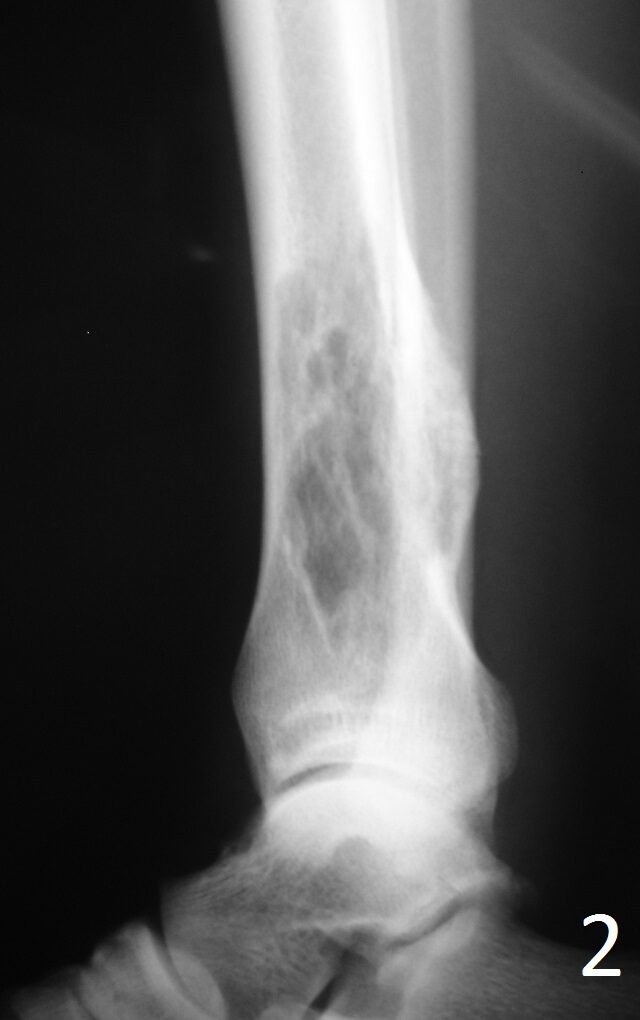

Plain x-ray (Fig. 1-2)

• Well-defined, lucent and expansile

• Possible cortical degradation

• Possible involvement of soft tissue

• More destructive, aggressive growth

• Shown by less-defined borders

• Pathologic fracture may occur

• Described as moth eaten

Fig. 1: AP and Lat (Fig. 2) Xray of tibia-fibula show a lucent distal tibia lytic lesion. Desmoplastic fibroma of bone often has thickened internal trabeculations and arises within the ceter of medullary canal.

Fig. 2